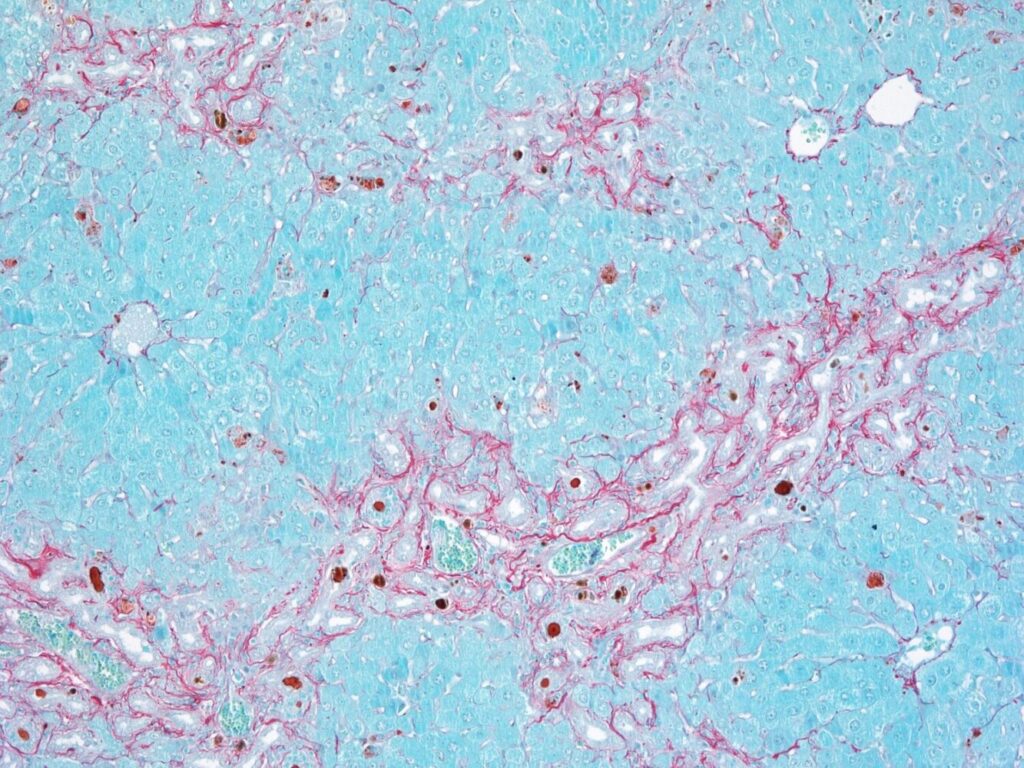

Fibrosis (rojo) en células del parénquima hepático (azul) como respuesta a una lesión celular. / Paula Sánchez. CNIO.

Si los conductos biliares dejan pasar los ácidos de la bilis, estos dañan el tejido hepático, que genera cicatrices para repararse. La acumulación de esas cicatrices provoca fibrosis.

Al llegar a zonas del hígado donde no deberían estar, los ácidos biliares activan otras células –las células estrelladas–, que generan cicatrices. Si estas se acumulan, dan lugar a la fibrosis hepática. Tanto la proliferación excesiva de las células BEC como la fibrosis pueden progresar hacia cirrosis hepática, una enfermedad grave y potencialmente mortal.